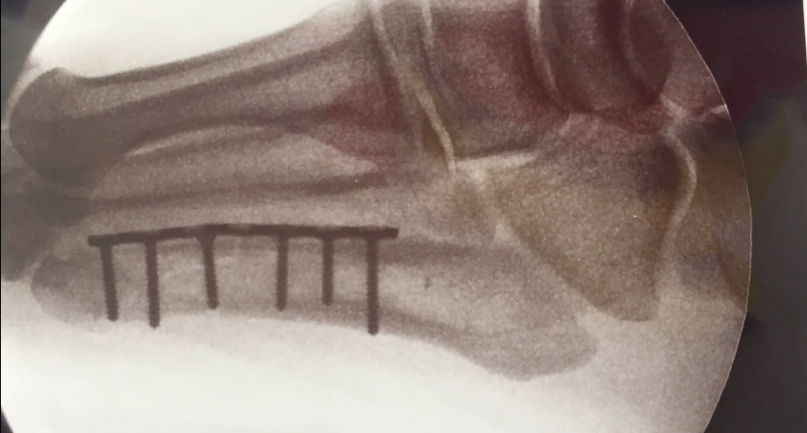

Schon nach nur einer Show erleben die wiedervereinten Guns N‘ Roses einen kleinen Rückschlag: Axl Rose hat sich den Fuß gebrochen und musste sich einer Operation unterziehen. Nun halten eine Metallplatte und Schrauben den Fuß zusammen.

@AxlRose: This is what can happen when you do something you haven’t done in nearly over 23 years, „Internal Fixation“ (ง’̀-‚́)ง